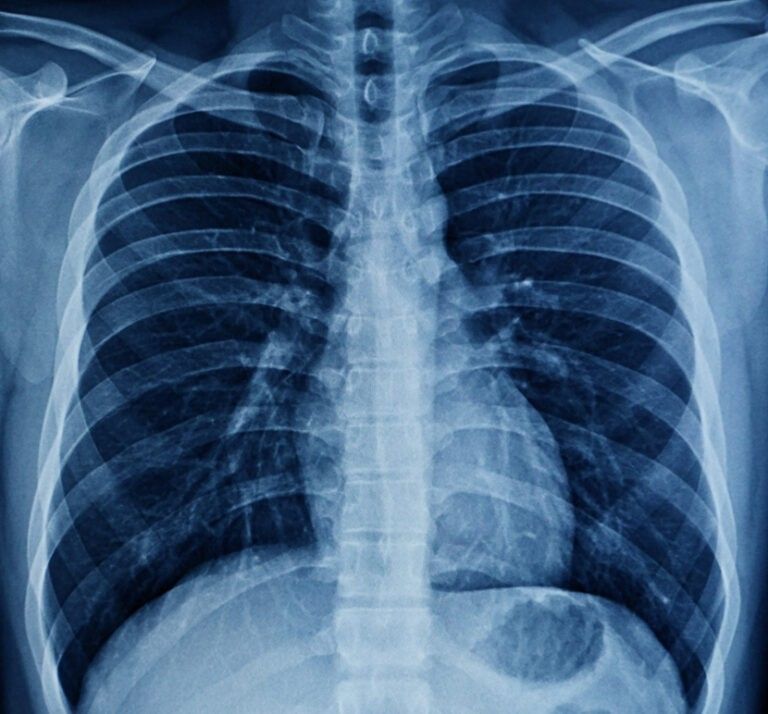

Our X-Ray Services

Home X-Ray Service

We provide convenient and reliable X-ray services right at your home, eliminating the need to travel to diagnostic centers. Our portable digital X-ray equipment ensures high-quality imaging with minimal discomfort.

Our services are designed to provide a seamless and stress-free diagnostic experience, eliminating the need for hospital visits and long waiting times. With comfortable X-ray services delivered directly at your home, patients can receive care in a familiar and relaxed environment.

We follow strict safety and hygiene protocols to ensure every procedure is secure and reliable. This service is especially ideal for senior citizens and patients with limited mobility, offering a quick and easy process from booking to report delivery. With advanced digital technology, we guarantee accurate and dependable reports to support timely medical decisions.